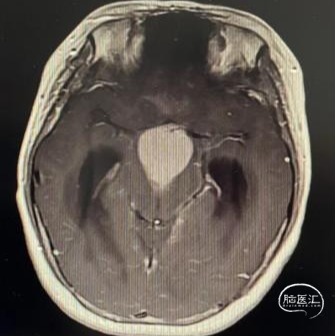

术后CT

术后MRI

在显微镜下经右侧额下联合终板入路全切除肿瘤,术后视力同术前。

病理检查:造釉细胞型颅咽管瘤伴钙化。